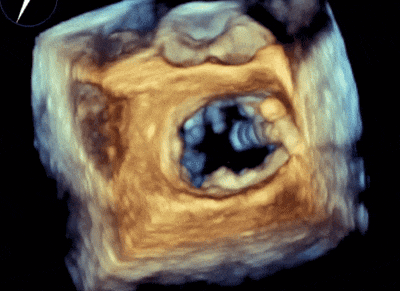

4.3D圖像調(diào)整夾子位置及鐘向;

5.下夾撤入心室后,捕獲夾合瓣葉,第一次夾合位置為3區(qū),夾合后2區(qū)一側(cè)殘余反流量2+,不符合術(shù)前預(yù)期,推開(kāi)上下夾;

6.調(diào)整夾子軸向后再次夾合,夾合后剩余反流量1+,符合術(shù)前預(yù)期,解離上下夾。

二尖瓣3區(qū)可見(jiàn)夾子強(qiáng)回聲,位置固定。